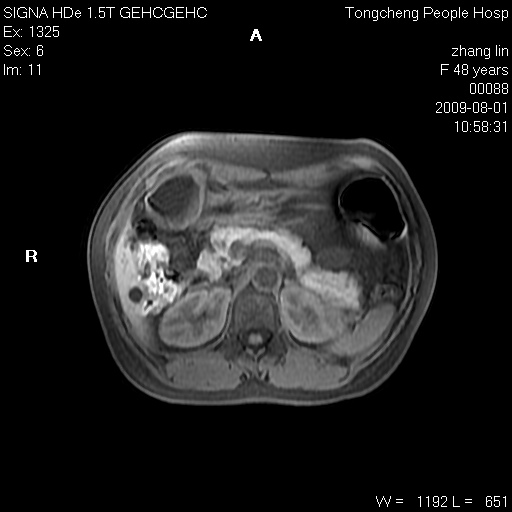

女,48岁。健康体检,彩超发现右肾占位性病变。平素健康。

临床诊断:右肾占位性病变,性质待定(囊肿?肿瘤?)。

上中腹部mr平扫+增强扫描,图像如下:

右肾上极见一类圆形病灶,t1wi呈等信号t2wi呈等高混杂信号,三期增强无强化,边界清---考虑囊肿出血。

同反相位均表现为等信号,病变无强化,考虑含蛋白的囊肿可能,弥散加权相或许有些帮助,

肝囊肿

慢性胆囊炎